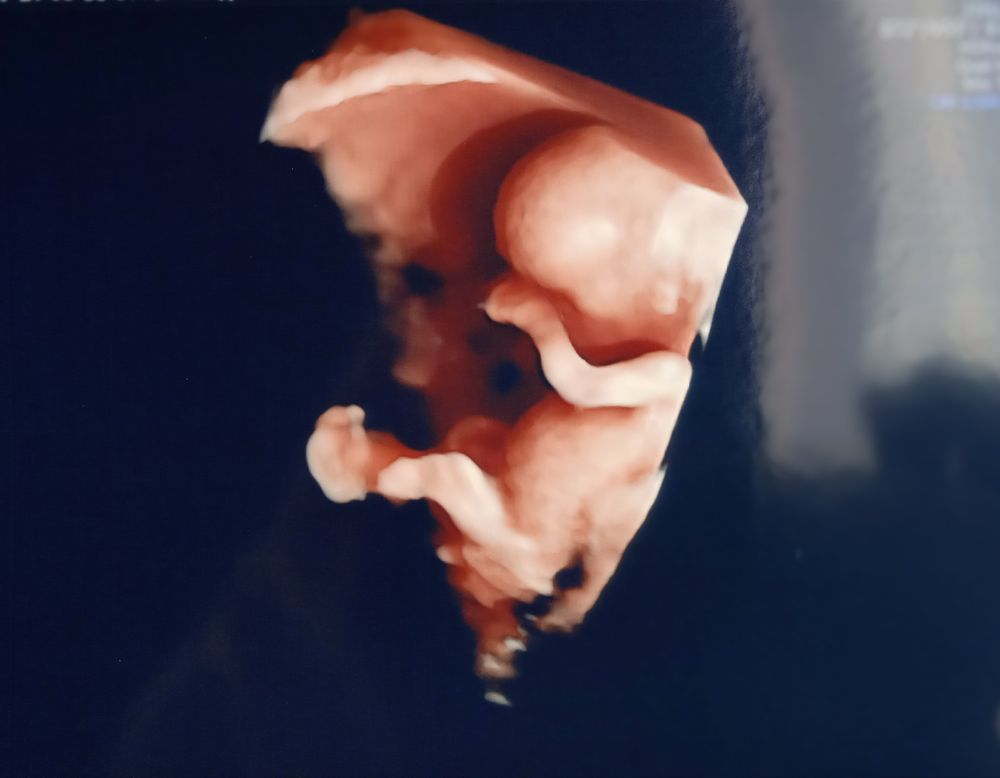

Анастасия, вот ещё 30,6 и 11,1 неделек, качество там отличное, аппарат последнего поколения